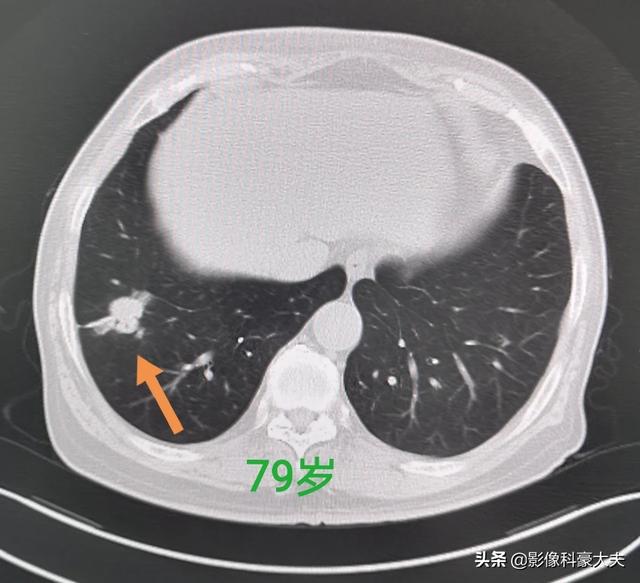

这位老人也比较幸运,右侧小肺癌,5年前做的的手术切除,今年已经84岁了。